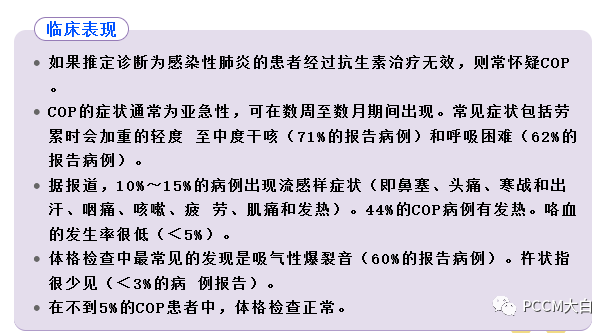

COP患者临床表现差异大,多数亚急性起病,发病早期常有发热、咳嗽、全身乏力等流感样症状,伴食欲减退和体质量下降,咯血、胸痛、夜间盗汗、关节痛及气胸较少见。多数患者表现为渐进性轻度呼吸困难,快速进展患者可见严重呼吸困难。大部分患者在双肺中下部可闻及吸气末Velcro啰音,部分患者可无肺部阳性体征。

实验室检查缺乏特异性,肺泡灌洗液(BALF)中细胞成分的变化对COP的诊断有一定的预测价值。除了BALF外,其他实验室辅助检查对COP的诊断帮助不大。由于临床表现缺乏特异性,COP诊断常常被延误。